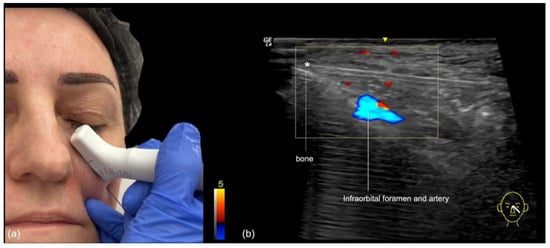

- Needle injection at 90 degrees: The authors primarily use this technique at the point of the malar eminence. This point is marked on the skin at the intersection of the lines connecting the lateral canthus to the oral commissure and the mid-tragus to the nasal ala (Figure 7). The area is then scanned with ultrasound (“scan before injecting”) to check for the presence of vessels or the foramen in the deep (periosteal) plane. If neither is present, a slow injection is performed following aspiration.

- Blunt cannula injection: To volumize the region, our preferred approach is the use of a cannula, which is kept in the deep subcutaneous plane. While the risk of occlusion is lower, there is still the possibility of compressing the infraorbital foramen with the filler, often resulting in persistent pain or paresthesia. A good strategy is to use ultrasound to identify the foramen in advance (Figure 8), mark it on the skin, and avoid this area during the cannula injection. The “scan while injecting” technique can also be used when the cannula is very close to the marked location of the foramen on the skin, to ensure that no injection occurs near it.